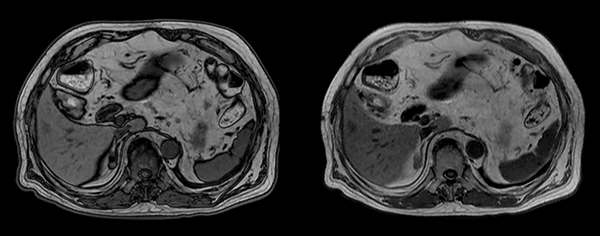

Axial T2w VISTA